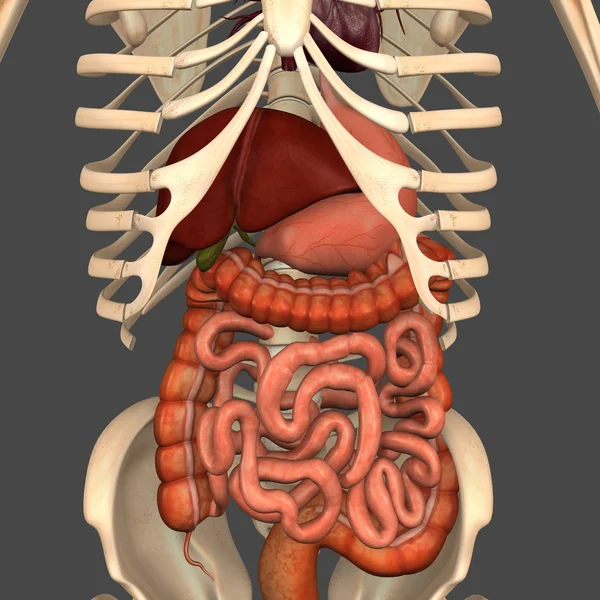

Sindirim Sistemi

Özel Boyut

(4096 x 4096, jpg)

MaviresimlemeİnsanKadınSağlıkkanİlaçAğızSolunumerkekkalpgövdeMidebiyolojiBilimSistemözetorgİskeletanatomiKas gücübeyinSistemlersindirimGerginakciğerlerkaraciğerBöbrekiskeletOrganlaranatomikBağırsaklarBağırsakKolondolaşımdalakBenzer İçerikler